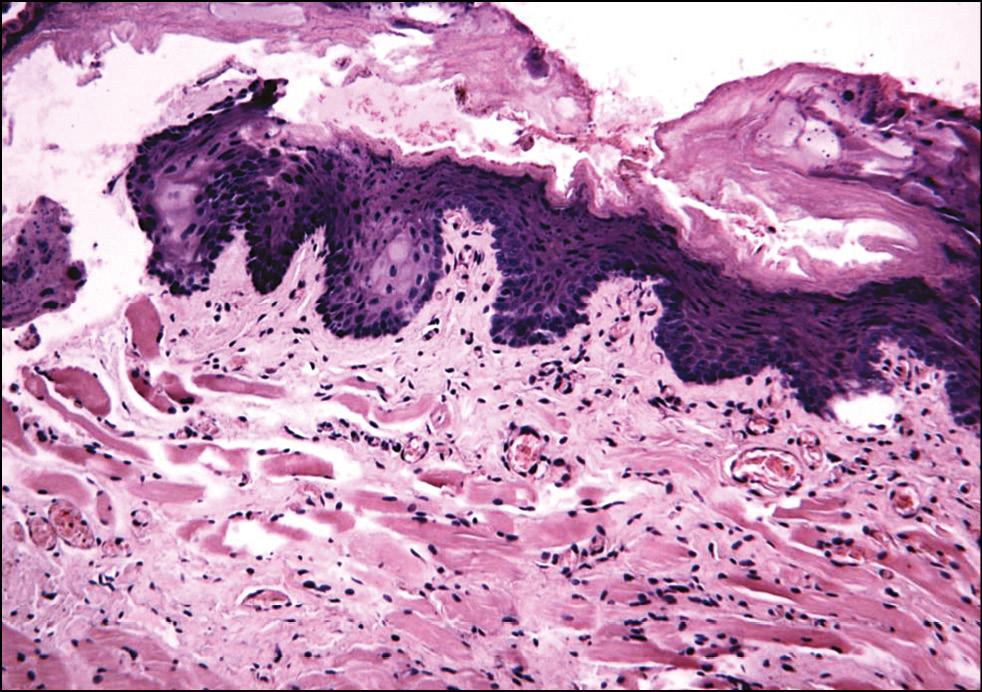

Рис. 6. Гистологическая картина кожи заушной области женщин через 30 мин после фотодинамической терапии. Окраска гематоксилином и эозином, x200.

Fig. 6. Histological picture of the skin behind the ear of women 30 minutes after photodynamic therapy. Hematoxylin and eosin staining, x200.

Рис. 7. Гистологическая картина кожи заушной области женщины через 3 дня после фотодинамической терапии. Окраска гематоксилином и эозином, x400.

Fig. 7. Histological picture of the skin behind the ear of women 3 days after photodynamic therapy. Hematoxylin and eosin staining, x400.

Рис. 8. Гистологическая картина кожи заушной области женщины через 20 дней после фотодинамической терапии. Окраска гематоксилином и эозином, x200.

Fig. 8. Histological picture of the skin behind the ear of women 20 days after photodynamic therapy. Hematoxylin and eosin staining, x200.

Подэтап 2А. Гистологическое исследование показало, что сразу после воздействия ФДТ (рис. 6) в коже обнаруживались единичные лейкоциты в толще эпидермиса и на его поверхности; ядра клеток эпидермиса и их цитоплазма на данном участке были набухшие, сосочки дермы несколько сглажены, рыхлая волокнистая соединительная ткань сосочкового слоя дермы отёчна. На третий день (рис. 7) после процедуры отмечено уменьшение количества набухших ядер в эпидермисе, заметны мелкоочаговые кровоизлияния в сетчатом слое дермы с перифокальной сосудистой реакцией и слабовыраженным отёком сетчатого слоя дермы. Спустя 20 дней (рис. 8) после воздействия заметна умеренная пролиферация клеток эпидермиса и дермы. Отмечается уплотнение коллагеновых волокон сетчатой дермы. Патологических изменений в эпидермисе, дерме, придатках кожи не обнаружено.

Таким образом, воздействие на кожу человека длиной волны 660 нм в течение 30 мин с использованием фотосенсибилизатора Сферометаллохлорина™ является безопасным и не приводит к развитию патологических реакций.